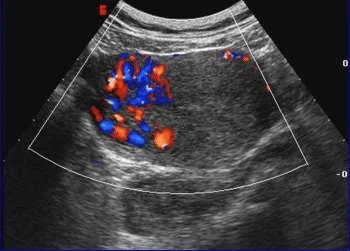

/attachments/image-1.webp)

/attachments/Molar-Pregnancy-(GTD)-ps10-2.webp)

Choriocarcinoma

- Enlarged uterus.

- With highly vascular mass that invades the endometrium.

- And sometimes with areas of necrosis & cystic lesions.